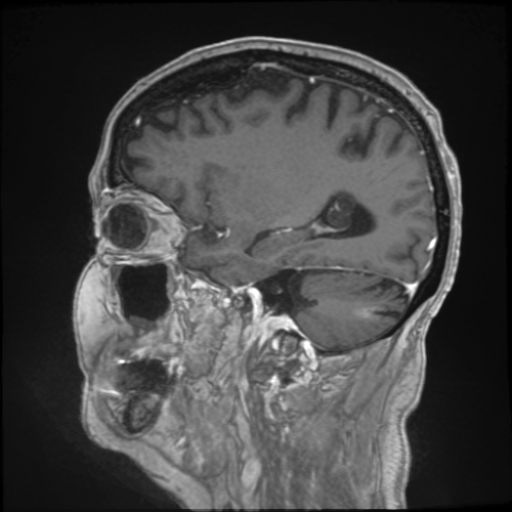

Refer to captionRefer to caption𝐱PCsubscript𝐱PC\mathbf{x}_{\mathrm{PC}}bold_x start_POSTSUBSCRIPT roman_PC end_POSTSUBSCRIPTRefer to captionRefer to caption𝐱LDsubscript𝐱LD\mathbf{x}_{\mathrm{LD}}bold_x start_POSTSUBSCRIPT roman_LD end_POSTSUBSCRIPTRefer to captionRefer to caption𝐱SDsubscript𝐱SD\mathbf{x}_{\mathrm{SD}}bold_x start_POSTSUBSCRIPT roman_SD end_POSTSUBSCRIPTRefer to captionRefer to captionAm-3D [14]Refer to captionRefer to captionPa-2.5D [8]Refer to captionRefer to caption𝐱^SDsubscript^𝐱SD\hat{\mathbf{x}}_{\mathrm{SD}}over^ start_ARG bold_x end_ARG start_POSTSUBSCRIPT roman_SD end_POSTSUBSCRIPT (ours)Refer to captionRefer to caption𝐱PCsubscript𝐱PC\mathbf{x}_{\mathrm{PC}}bold_x start_POSTSUBSCRIPT roman_PC end_POSTSUBSCRIPTRefer to captionRefer to caption𝐱LDsubscript𝐱LD\mathbf{x}_{\mathrm{LD}}bold_x start_POSTSUBSCRIPT roman_LD end_POSTSUBSCRIPTRefer to captionRefer to caption𝐱SDsubscript𝐱SD\mathbf{x}_{\mathrm{SD}}bold_x start_POSTSUBSCRIPT roman_SD end_POSTSUBSCRIPTRefer to captionRefer to captionAm-3D [14]Refer to captionRefer to captionPa-2.5D [8]Refer to captionRefer to caption𝐱^SDsubscript^𝐱SD\hat{\mathbf{x}}_{\mathrm{SD}}over^ start_ARG bold_x end_ARG start_POSTSUBSCRIPT roman_SD end_POSTSUBSCRIPT (ours)Refer to captionRefer to caption𝐱PCsubscript𝐱PC\mathbf{x}_{\mathrm{PC}}bold_x start_POSTSUBSCRIPT roman_PC end_POSTSUBSCRIPTRefer to captionRefer to caption𝐱LDsubscript𝐱LD\mathbf{x}_{\mathrm{LD}}bold_x start_POSTSUBSCRIPT roman_LD end_POSTSUBSCRIPTRefer to captionRefer to caption𝐱SDsubscript𝐱SD\mathbf{x}_{\mathrm{SD}}bold_x start_POSTSUBSCRIPT roman_SD end_POSTSUBSCRIPTRefer to captionRefer to captionAm-3D [14]Refer to captionRefer to captionPa-2.5D [8]Refer to captionRefer to caption𝐱^SDsubscript^𝐱SD\hat{\mathbf{x}}_{\mathrm{SD}}over^ start_ARG bold_x end_ARG start_POSTSUBSCRIPT roman_SD end_POSTSUBSCRIPT (ours)Refer to captionRefer to caption𝐱PCsubscript𝐱PC\mathbf{x}_{\mathrm{PC}}bold_x start_POSTSUBSCRIPT roman_PC end_POSTSUBSCRIPTRefer to captionRefer to caption𝐱LDsubscript𝐱LD\mathbf{x}_{\mathrm{LD}}bold_x start_POSTSUBSCRIPT roman_LD end_POSTSUBSCRIPTRefer to captionRefer to caption𝐱SDsubscript𝐱SD\mathbf{x}_{\mathrm{SD}}bold_x start_POSTSUBSCRIPT roman_SD end_POSTSUBSCRIPTRefer to captionRefer to captionAm-3D [14]Refer to captionRefer to captionPa-2.5D [8]Refer to captionRefer to caption𝐱^SDsubscript^𝐱SD\hat{\mathbf{x}}_{\mathrm{SD}}over^ start_ARG bold_x end_ARG start_POSTSUBSCRIPT roman_SD end_POSTSUBSCRIPT (ours)Refer to captionRefer to caption𝐱PCsubscript𝐱PC\mathbf{x}_{\mathrm{PC}}bold_x start_POSTSUBSCRIPT roman_PC end_POSTSUBSCRIPTRefer to captionRefer to caption𝐱LDsubscript𝐱LD\mathbf{x}_{\mathrm{LD}}bold_x start_POSTSUBSCRIPT roman_LD end_POSTSUBSCRIPTRefer to captionRefer to caption𝐱SDsubscript𝐱SD\mathbf{x}_{\mathrm{SD}}bold_x start_POSTSUBSCRIPT roman_SD end_POSTSUBSCRIPTRefer to captionRefer to captionAm-3D [14]Refer to captionRefer to captionPa-2.5D [8]Refer to captionRefer to caption𝐱^SDsubscript^𝐱SD\hat{\mathbf{x}}_{\mathrm{SD}}over^ start_ARG bold_x end_ARG start_POSTSUBSCRIPT roman_SD end_POSTSUBSCRIPT (ours)Refer to captionRefer to caption𝐱PCsubscript𝐱PC\mathbf{x}_{\mathrm{PC}}bold_x start_POSTSUBSCRIPT roman_PC end_POSTSUBSCRIPTRefer to captionRefer to caption𝐱LDsubscript𝐱LD\mathbf{x}_{\mathrm{LD}}bold_x start_POSTSUBSCRIPT roman_LD end_POSTSUBSCRIPTRefer to captionRefer to caption𝐱SDsubscript𝐱SD\mathbf{x}_{\mathrm{SD}}bold_x start_POSTSUBSCRIPT roman_SD end_POSTSUBSCRIPTRefer to captionRefer to captionAm-3D [14]Refer to captionRefer to captionPa-2.5D [8]Refer to captionRefer to caption𝐱^SDsubscript^𝐱SD\hat{\mathbf{x}}_{\mathrm{SD}}over^ start_ARG bold_x end_ARG start_POSTSUBSCRIPT roman_SD end_POSTSUBSCRIPT (ours)Refer to captionRefer to caption𝐱PCsubscript𝐱PC\mathbf{x}_{\mathrm{PC}}bold_x start_POSTSUBSCRIPT roman_PC end_POSTSUBSCRIPTRefer to captionRefer to caption𝐱LDsubscript𝐱LD\mathbf{x}_{\mathrm{LD}}bold_x start_POSTSUBSCRIPT roman_LD end_POSTSUBSCRIPTRefer to captionRefer to caption𝐱SDsubscript𝐱SD\mathbf{x}_{\mathrm{SD}}bold_x start_POSTSUBSCRIPT roman_SD end_POSTSUBSCRIPTRefer to captionRefer to captionAm-3D [14]Refer to captionRefer to captionPa-2.5D [8]Refer to captionRefer to caption𝐱^SDsubscript^𝐱SD\hat{\mathbf{x}}_{\mathrm{SD}}over^ start_ARG bold_x end_ARG start_POSTSUBSCRIPT roman_SD end_POSTSUBSCRIPT (ours)

Figure 5: Qualitative comparison for test samples of the SLD-METS dataset. The zooms highlight the metastasis location. By design, our approach adds the CE signal to the input image, thereby preserving its image quality. The input images at the top have the same resolution, while they strongly differ at the bottom. Thus, the image quality of our output 𝐱^SDsubscript^𝐱SD\hat{\mathbf{x}}_{\mathrm{SD}}over^ start_ARG bold_x end_ARG start_POSTSUBSCRIPT roman_SD end_POSTSUBSCRIPT is poor in the bottom row and decent in the top row.

The average mean and maximal relative enhancement across the 351351351351 lesions is listed in the c¯¯𝑐\overline{c}over¯ start_ARG italic_c end_ARG and c^^𝑐\widehat{c}over^ start_ARG italic_c end_ARG columns of Table 1. Our approach significantly improves the predicted CE strength compared to Am-3D and Pa-2.5D. Note that c¯¯𝑐\overline{c}over¯ start_ARG italic_c end_ARG is not only sensitive to the CE strength (as c^^𝑐\widehat{c}over^ start_ARG italic_c end_ARG), but also to a lesion’s internal morphology and border delineation. A qualitative comparison of a typical lesion is visualized in the zooms at the top row of Figure 5. While Am-3D struggles to predict the internal morphology of the lesions, the CE strength of Pa-2.5D is too low. In contrast, our approach predicts the right contrast strength, morphology, and boundary of the lesion.

Table 1 contains a quantitative evaluation of the considered dose reduction approaches. The PSNRI𝐼{}_{I}start_FLOATSUBSCRIPT italic_I end_FLOATSUBSCRIPT column reports the average score of the 48484848 test samples and the PSNRL𝐿{}_{L}start_FLOATSUBSCRIPT italic_L end_FLOATSUBSCRIPT represents the mean of all 351351351351 lesions in the test set. While our approach is inferior in terms of PSNR score on the entire image, we significantly outperform all competitors on lesions. A t𝑡titalic_t-test of our approach and the closest competitor yielded the p𝑝pitalic_p-values presented in the last row. The worse PSNR scores on the entire images of our model originate from the low resolution of many pre-contrast images in the SLD-METS dataset compared to the available post-contrast images. By design, our model only focuses on the accurate prediction of the CE signal. Thus, it cannot change the overall image quality of the input images. Taking this into account, the PSNRI𝐼{}_{I}start_FLOATSUBSCRIPT italic_I end_FLOATSUBSCRIPT score of our implicit ground truth 𝐱PC+𝐲SDsubscript𝐱PCsubscript𝐲SD\mathbf{x}_{\mathrm{PC}}+\mathbf{y}_{\mathrm{SD}}bold_x start_POSTSUBSCRIPT roman_PC end_POSTSUBSCRIPT + bold_y start_POSTSUBSCRIPT roman_SD end_POSTSUBSCRIPT is 42.4842.4842.4842.48dB, which is the upper bound for our approach and below the 44.0244.0244.0244.02dB of Ps-2.5D. This can also be seen in the qualitative comparison depicted in the bottom row of Figure 5. The image quality of 𝐱PCsubscript𝐱PC\mathbf{x}_{\mathrm{PC}}bold_x start_POSTSUBSCRIPT roman_PC end_POSTSUBSCRIPT is worse compared to 𝐱SDsubscript𝐱SD\mathbf{x}_{\mathrm{SD}}bold_x start_POSTSUBSCRIPT roman_SD end_POSTSUBSCRIPT. In particular, the boundaries between the white and gray matter or the ventricles are hardly visible in 𝐱PCsubscript𝐱PC\mathbf{x}_{\mathrm{PC}}bold_x start_POSTSUBSCRIPT roman_PC end_POSTSUBSCRIPT as it was acquired with a lower in-plane resolution. In contrast to Am-3D and Pa-2.5D, our approach cannot overcome this lack of resolution. Nevertheless, the CE signal is also well captured by our approach.